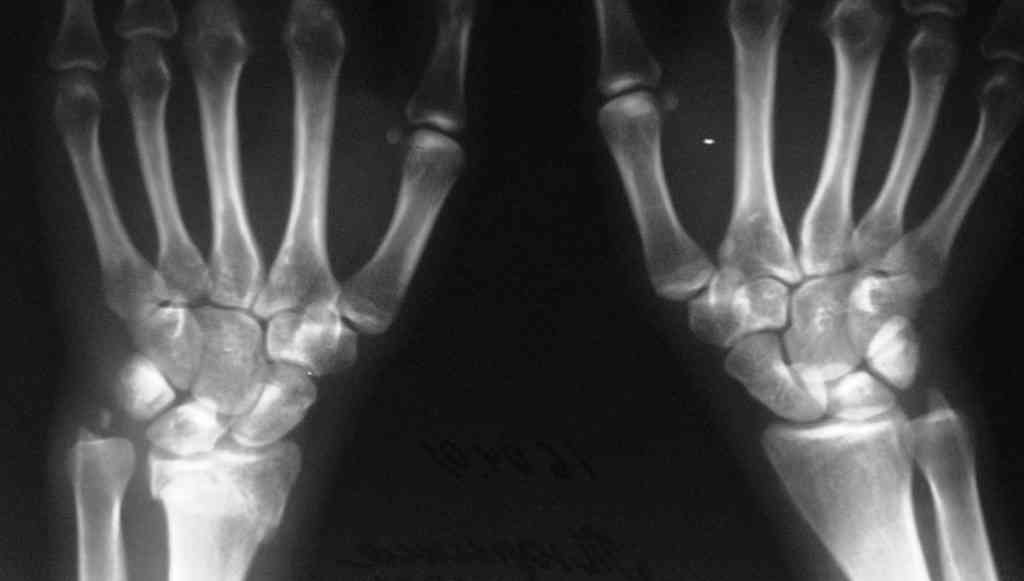

Спице-стержневой аппарат с компактотомией лучевой кости, костная пластика локтевой с удалением пластины. Не комфортно, но больше шансов на благоприятный исход. Заканчиваю лечение с похожей деформацией лучевой кости.